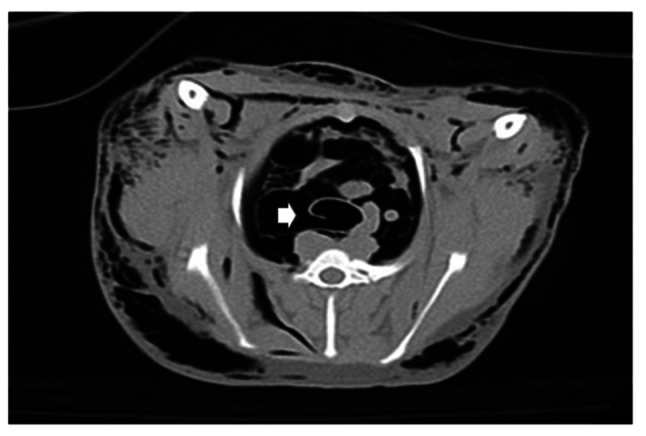

Materials and methods: A double-wire woven nitinol stent was handmade using a cross-and-hook knitting method. The fabricated endotracheal stent was 2-3 mm larger than the internal diameter of the ruptured trachea. The clinical signs and respiratory pattern, image diagnoses (radiography and computed tomography), and tracheoscopy results after endotracheal stenting were assessed for six months.

Results: The lateral cervical radiographs showed that the intratracheal stent was properly placed without migration or stent fracture at the insertion site. After two to three weeks of tracheal stenting, the coughing and dyspnea signs revolved, and the normal activities in all dogs were resumed.